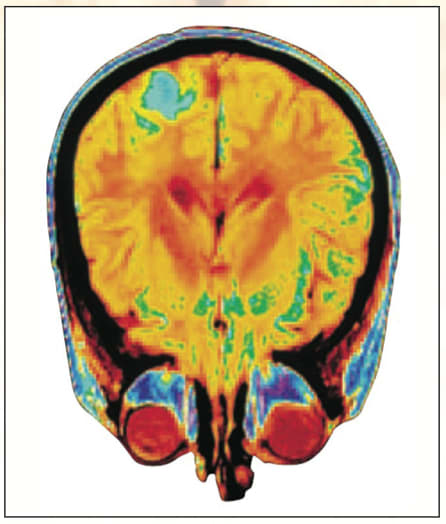

Several imaging modalities are used in neural imaging, depending on the measurements required. Most commonly, relatively low-resolution methods such as magnetic resonance imaging (MRI) and diffusion tensor imaging (DTI) are used individually or in combination to probe areas of neural activity over time within living subjects. This longitudinal image data allows changes in activity to be mapped over time. Intensity maps of MRI-detected signals are typically interpreted qualitatively by physicians to localize regions of activity or damage. DTI data is generated with gradients of magnetic fields applied over a range of directions so that anisotropic diffusion of dyes can be computed using a 3 × 3 mathematical operator called a tensor. Physicians can use the resulting image to map neural connections and areas of injury at much higher resolutions than with traditional MRI.

Structures and dynamic features measured in neural imaging are typically represented as 3D maps that the user can interact with in real time. The scale of the data may range from millimeters to microns and contain different information relating to its physical structure and molecular composition. Visualization tools may be tailored to users’ needs. In many Web-based atlases, the user can view 3D structures interactively. More sophisticated image data such as that collected by DTI often employs a combination of pseudo-coloring and annotation using vector fields to show structures detected by anisotropic diffusion. However, in a research setting, the user requirements for data visualization are typically far more sophisticated. The most critical and effective visualization environments, such as the Mouse BIRN Atlasing Toolkit (www.loni.ucla.edu/software), are linked to analysis tools and databases containing repositories of images and extracted data. This capability enables iterative analysis and review of image processing methods being developed or being applied to new data. Often rate-limiting steps include querying the data repository and moving large quantities of image and calculated table data from servers to desktops.